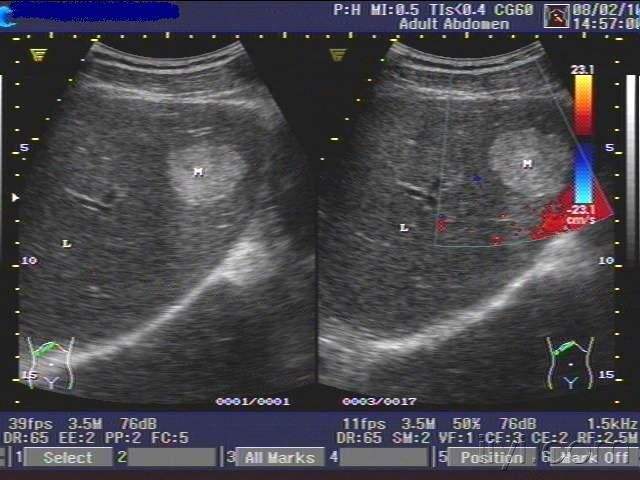

患者女,45岁,肝右叶肿物,考虑血管瘤,请各位老师指导,感谢 - 超声医学

肝血管瘤:超声造影诊断敏感性高